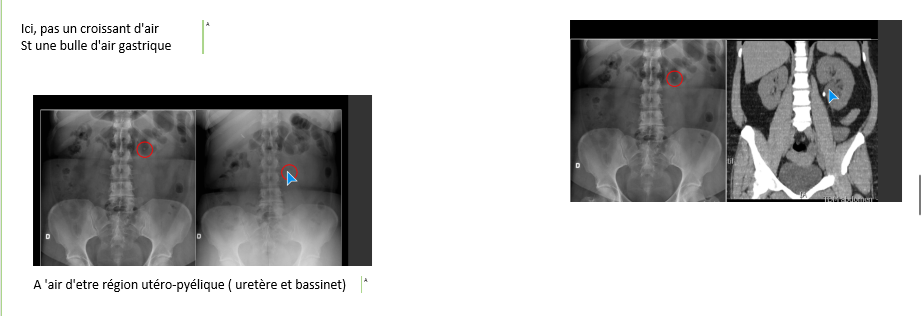

A

calcification,lithiase urinaire